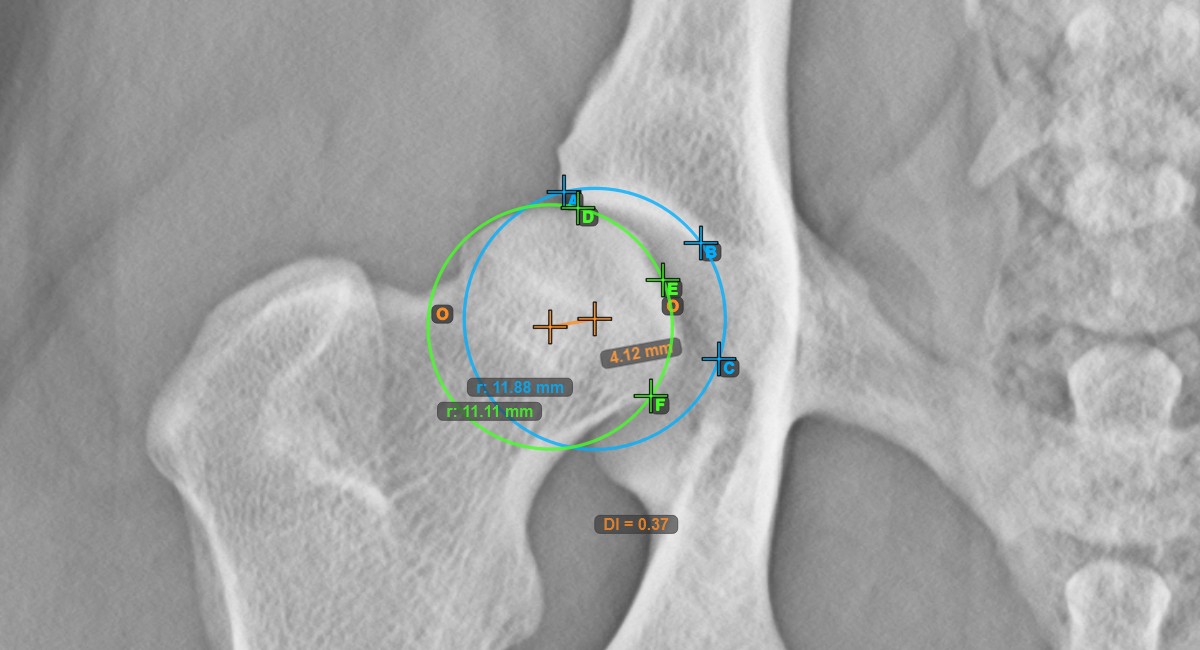

The Hip Distraction Index will be automatically calculated as the ratio between the distance between the two origos and the radius of the circle along the articular surface of the Caput Femoris.

The image below represents a typical placement of the three points on the articular surface of the Caput Femoris.